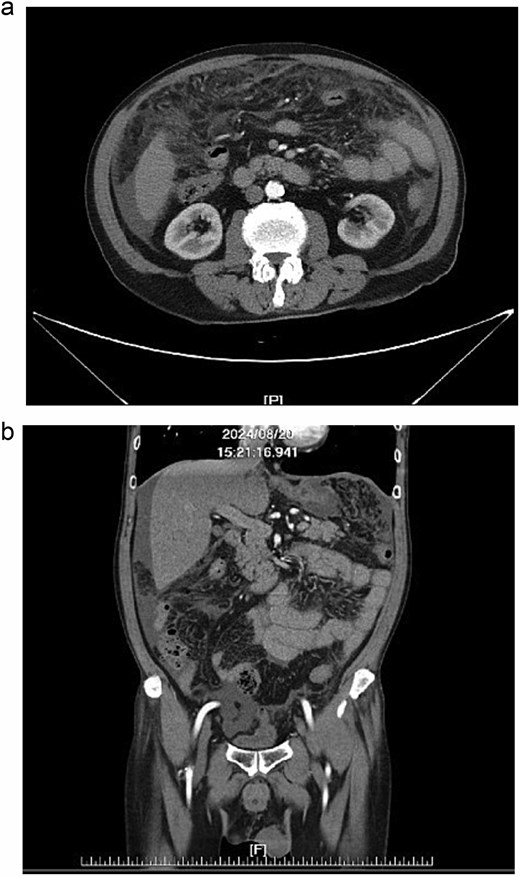

Further diagnostic evaluation with computed tomography (CT) of the abdomen and lungs was conducted. The abdominal CT revealed mild peritoneal thickening with multiple miliary nodules and omental cake with ascites (Fig. 1a and b), while the lung CT demonstrated multifocal of patches of centrilobular nodules and tree-in-bud in bilateral lungs (Fig. 2a, b).

(a, b) Abdominal CT, peritoneal thickening with multiple miliary nodules and omental cake with ascites.